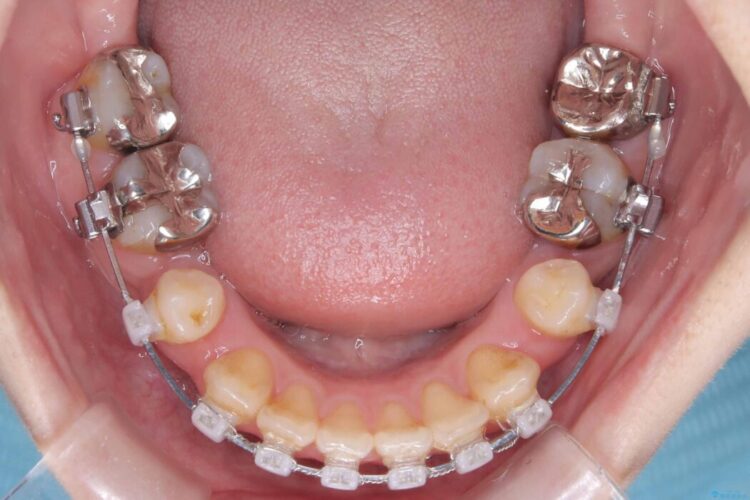

- 矯正装置:ワイヤー矯正(クリア装置)

開咬、叢生、八重歯が気になるとご来院された患者様です。

精密検査の結果、上顎左右4番および下顎左右5番の計4本を抜歯し、目立ちにくいクリア装置にて治療を行いました。

また、虫歯があったので、矯正開始前に虫歯治療を行っております。

気になっていたガタつきや開咬が改善され、見た目だけでなく咬み合わせの機能面も大きく向上し、大変ご満足いただけました。